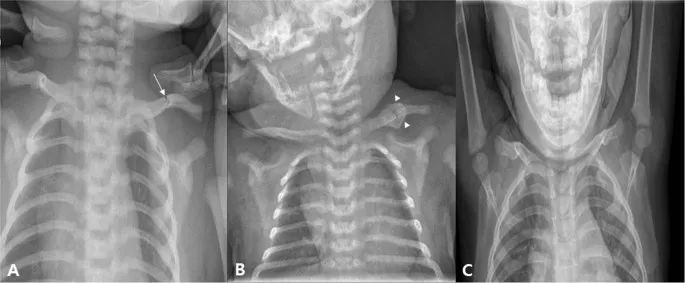

- Clavicular Fracture: Most common birth fracture, often mid-clavicle.

- Signs: Crepitus, palpable bony irregularity, asymmetric Moro reflex, infant irritable on handling.

- Management: Gentle handling, immobilize arm (pin sleeve to chest). Heals rapidly with callus.

⭐ The clavicle is the most frequently fractured bone during labor and delivery, often presenting with an absent Moro reflex on the affected side.

- Phrenic nerve palsy (C3-C5) results in respiratory distress and unilateral diaphragmatic elevation on X-ray.